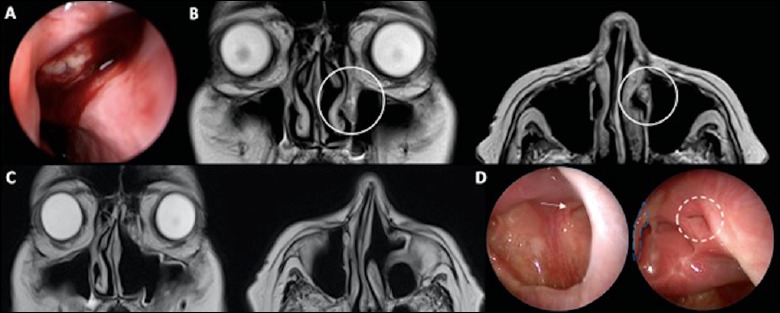

Exclusive or combined endoscopic approach to tumours of the lower lacrimal pathway: review of the literature.

下泪腺通路肿瘤的独家或联合内窥镜方法:文献综述。